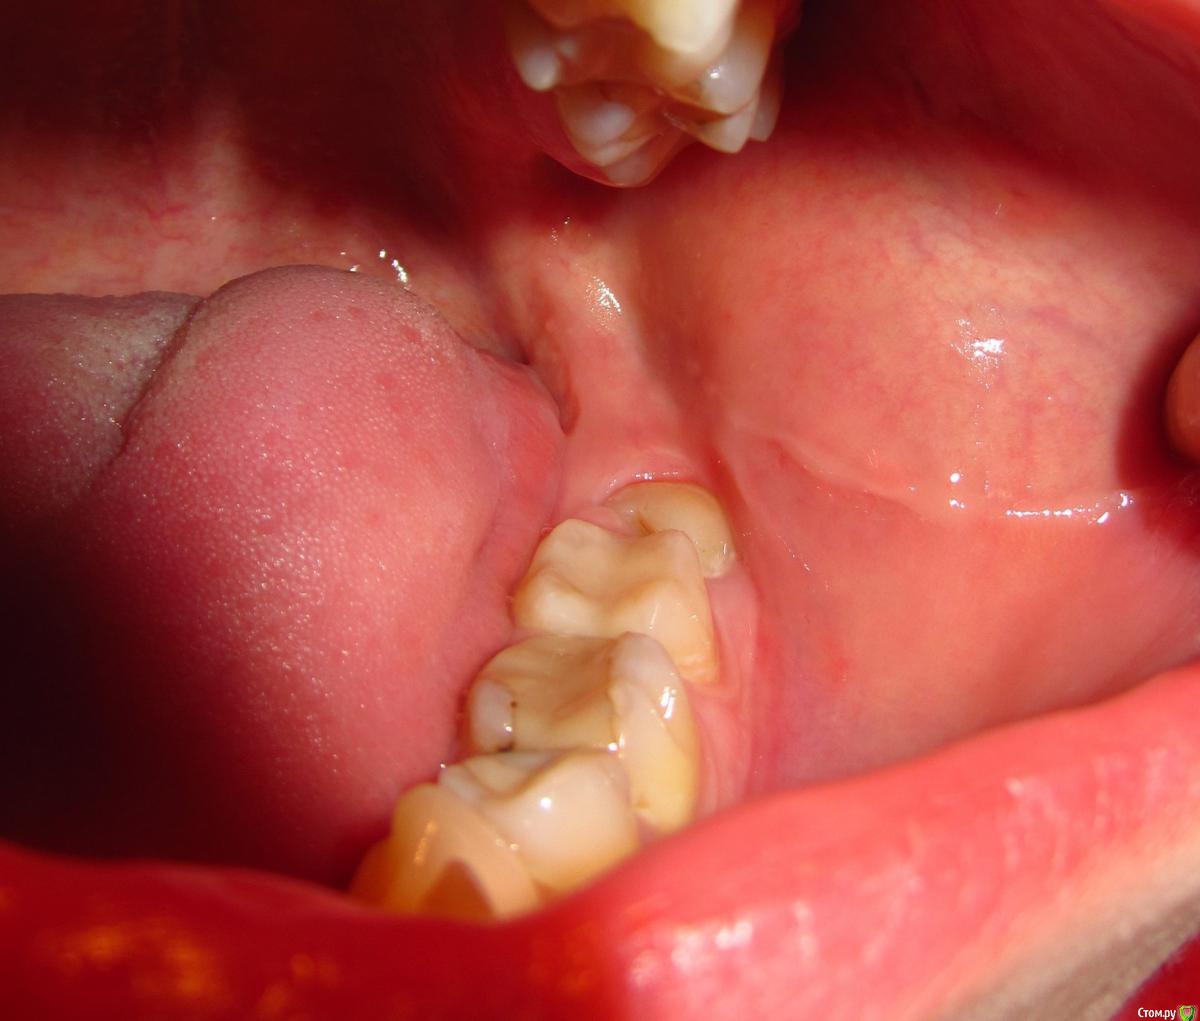

aqua1 Опубликовано 8 февраля, 2015 Поделиться Опубликовано 8 февраля, 2015 Добрый день! История моя давняя и до сих пор не решена….Где-то в 2007 году удалили в нижней 5-ке нерв, но зуб иногда «простреливал» при случайном накусывании по ночам. Подозреваю, что неудачное лечение могло быть связано с тем, что немного передержали лекарство, так как врач был в отпуске..Через полгода, в 2008 году на десне между 5 и 6 образовался бугорок, снимок показал воспаление на корне. Так как каналы на снимке были запломбированы хорошо, сказали что нет смысла их перелечивать, и зуб придётся удалить(( Естественно, меня такой поворот не устраивал, зуб был хорошо сохранен, никогда не беспокоил, и лечение кариеса изначально было просто профилактическим, но канал оказался слишком близко... Второй вариант был антибиотики, образовался свищ, а вскоре всё зажило и припухлость полностью спала (хотя на снимке 2009 года ситуация не изменилась).Ни зуб, ни дёсны не беспокоили меня абсолютно до весны 2012 года, когда после ветреной погоды, зуб поныл 2 дня и образовалась даже не припухлость, а затвердевшая дуга вдоль 6-8 зубов. Боли и воспаления не было. Испугавшись, что это будет расти и дальше такими же темпами, поехала в стоматологию, где терапевт отправила меня к хирургу, у которого было 2 варианта – резать или вырывать. На новом снимке никаких изменений опять замечено не было.. Десну разрезали между 5 и 6, гноя не было, потом отёк сошёл, а затвердение нет.В настоящий момент оно особо не беспокоит, только иногда ощущается в челюсти, асимметрии лица тоже вроде не заметно. В 2014 году начала активно лезть полулежачая восьмерка, без боли и воспаления. Затвердевшая дуга на десне начинается под 6-м зубом и плавно уходит за эту 8-ку. По случаю всего этого в январе 2015 сделали панорамный снимок всей этой красоты.Очень нужны ваши советы!1) Обязательно ли удалять эту 5-ку или как её лечить? Сойдет ли затвердение на десне после удаления? Что это вообще может быть?2) Я так понимаю, что 8-ка на удаление. Стоит ли немного подождать, пока она вылезет побольше, чтобы легче её удалить?Заранее спасибо. Прилагаю всю историю в рентгенах, а также фото, как это выглядит сейчас вживую. Ссылка на комментарий

aqua1 Опубликовано 8 февраля, 2015 Автор Поделиться Опубликовано 8 февраля, 2015 (изменено) Разъяснения по снимкам:1) весна 2008 года - начало2) 2009 год3) весна 2012 года - сразу после обострения и появления отвердевшей десны4) свежий снимок 2015 года5) так выглядит зуб мудрости4) зубы и десна в обычном состоянии7) и 8) - изображения отвердевшей дуги на десне вдоль 6, 7 и 8 зубов (т.е. та область, что между зубами и пальцем) Изменено 8 февраля, 2015 пользователем aqua1 Ссылка на комментарий